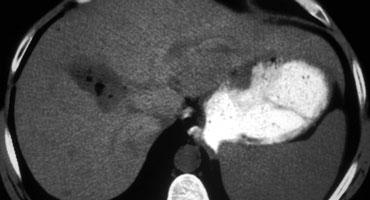

Di căn giảm mạch biểu hiện là các tổn thương giảm tỷ trọng trong thì tĩnh mạch cửa muộn. Lưu ý có một số ngấm thuốc dạng viền ở vùng ngoại vi còn sống của các ổ di căn.

Thì tĩnh mạch cửa

Chụp thì tĩnh mạch cửa dựa trên nguyên lý ngược lại.

Chúng ta chụp gan khi gan đã được nạp đầy thuốc cản quang qua tĩnh mạch cửa để phát hiện các khối u giảm mạch (hình).

Thời điểm tốt nhất để bắt đầu chụp là khoảng 75 giây, đây là thì tĩnh mạch cửa muộn, vì sự ngấm thuốc của tĩnh mạch cửa đã bắt đầu từ 35 giây trong thì động mạch muộn.

Thì tĩnh mạch cửa muộn này còn được gọi là thì gan vì lúc này các tĩnh mạch gan đã phải ngấm thuốc.